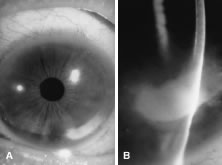

In the early stages of infection, filamentous fungi produce signs that are readily distinguishable from yeast or bacterial keratitis. The most distinctive sign is the presence of delicate, fine, feathery, opalescent, gray-white or yellow-white material in the anterior stroma, surrounded by scant cellular infiltrate or edema (Fig. 1). The epithelium may be intact. The overlying epithelium may be granular and the surface elevated and irregular in contour. Linear infiltrates typically extend into the adjacent stroma. Multiple discrete opacities may develop outside the perimeter of the principal focus of inflammation, either separated by clear stroma or linked by fine linear collections of inflammatory cells and material (Figs. 2 and 3). In the absence of inflammation in the adjacent stroma, branching hyphal fragments may be visualized by biomicroscopy (Figs. 4 and 5). Confocal microscopy may also detect hyphal elements within the stroma.28,29 Peripheral infection resembles noninfectious marginal infiltrative and ulcerative keratitis (Fig. 6). Multifocal keratitis may develop after contact lens wear or injury by multiple projectiles (Fig. 7). In the early stages, iritis is present and the intraocular pressure remains normal. Inappropriate, empirical therapy of fungal keratitis with topical fluoroquinolone or aminoglycoside antibiotics may suppress or eliminate the superficial elements but allow extension of the organisms into the stroma because these agents may possess selective antifungal activity.4,30,31

There is no distinguishing clinical sign by which to recognize the genus or species of the infectious filamentous fungus. F. solani is the most virulent organism and typically produces rapidly progressive infection characterized by epithelial and stromal ulceration, dense stromal necrosis, abundant cellular infiltrate, and edema in the adjacent stroma and hypopyon (Figs. 8 and 9). Delicate feathery components are transient. Individual hyphal fragments are rarely visualized. Infection by certain species of Aspergillus and Scedosporium (Figs. 10 and 11) resembles F. solani keratitis and progresses rapidly. Infection by less virulent organisms, such as Curvularia and Alternaria species, produces small, focal (less than 3-mm diameter) areas of nonnecrotizing stromal inflammation with delicate feathery borders (see Fig. 1 and Fig. 12). Macroscopic pigmentation may develop in keratitis caused by Alternaria, Curvularia, and other dematiaceous fungi (Fig. 13).4,11,14 The central component may progress to dense, opaque, gray-white suppuration in the deep stroma without enlargement in total area and may be accompanied by mild inflammation in the adjacent stroma. Iritis is minimal to moderate. Infection caused by other, relatively less virulent organisms resembles herpes simplex or noninfectious keratitis (Fig. 14).